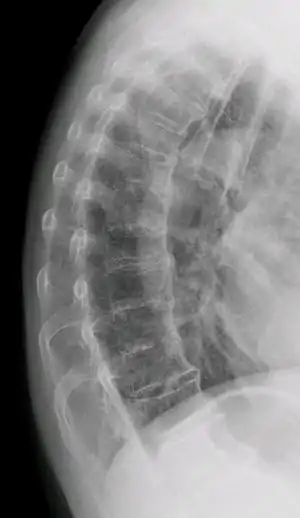

"Melted candle wax" appearance of calcification and ossification in diffuse idiopathic skeletal hyperostosis (DISH). Note the preponderance on the patient's left side (right side of image).